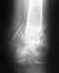

перелом со смещением

осколочный перелом лучевой кости со смещением...отростка левого локтя со смещением.

все что смогла понять.мне 48.сегодня упала.наложили шину.в понедельник на операцию.какая пластина или спица должна быть.волнует финансовая сторона.